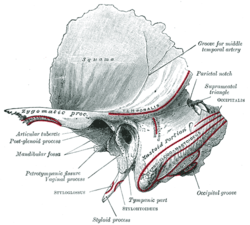

Animation..gif) Animation. Left temporal bone.

Animation. Left temporal bone.- Base of skull. Mastoid process labeled at middle left.

Base of skull. Muscle attachments are shown in red lines. Side view of head, showing surface relations of bones. (Mastoid process labeled near center.)

Side view of head, showing surface relations of bones. (Mastoid process labeled near center.)